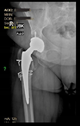

The guiding wire was inserted and controlled with fluoroscopy flashes (Figure 4). The drilling and reaming were carried out in accordance with the recommendations:

Figure 4.

The biocompatible aiming device after insertion of the guiding wire.

The radiological examination allowed us to verify the close bone-to-implant contact and the unchanged position of the implant during follow-up.

In all the cases operated with the above-described targeting procedure, the stems of the cups remained between the cortical bone surfaces without perforation of the linea terminalis, as shown by postoperative radiographs. There were no complicated surgical situations. In 16 cases, the wound healings were uneventful, and the hips were able to bear weight again after postoperative rehabilitation.